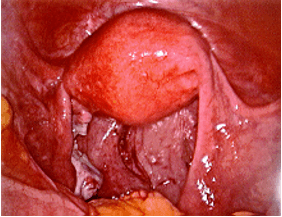

The photos below show several different types of ovarian masses:

Left photo – a large solid mass arising from the left ovary – an ovarian fibroma. Right photo – the fibroma can be seen growing from the lower part of the otherwise normal left ovary.

The same patient after laparoscopic removal of the left ovarian fibroma.